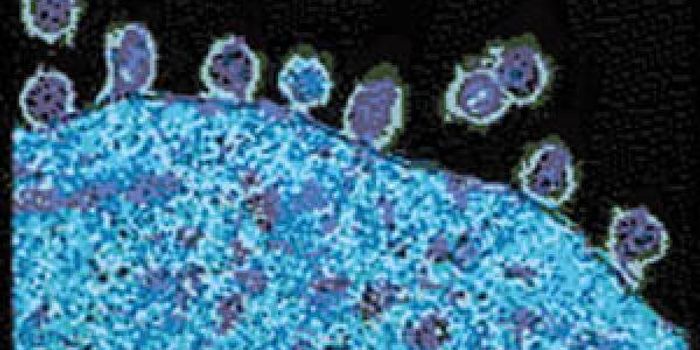

DEC 10, 2015ImmunologySuperior technology brings us novel images of cancer cells and lymphocytes this week, and now scientists can learn more ...